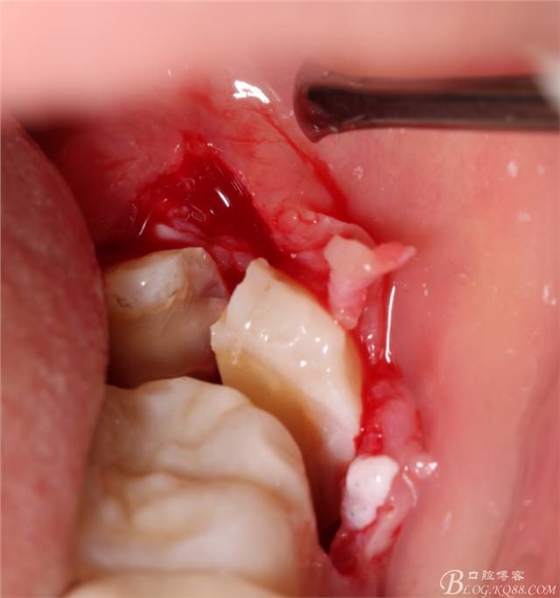

切開:角形切口,這個位置切開我喜歡更易操作12#刀。

鈍性翻辨露冠

角度鍋輪機結(jié)合冷鹽水冷卻分冠

分冠完成

取出阻力部分冠

在取出阻力冠后,嘗試性看能取出全部的牙體不,就是取不出也能整體撬動牙根。